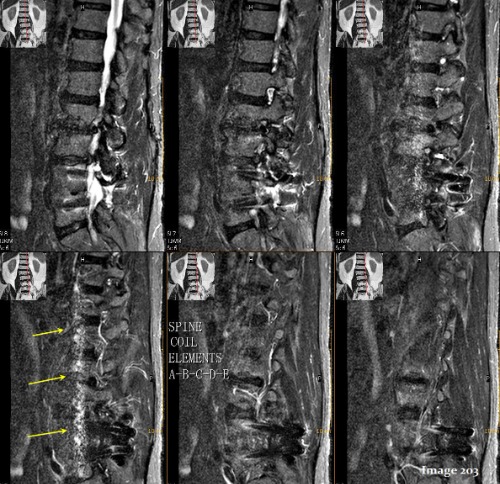

The yellow arrows in Image 203 identify a bright, ribbon-like artifact near the edge of the FOV. This is known as an:

A. Magic angle

B. Dielectric

C. Aliasing

D. Annefact